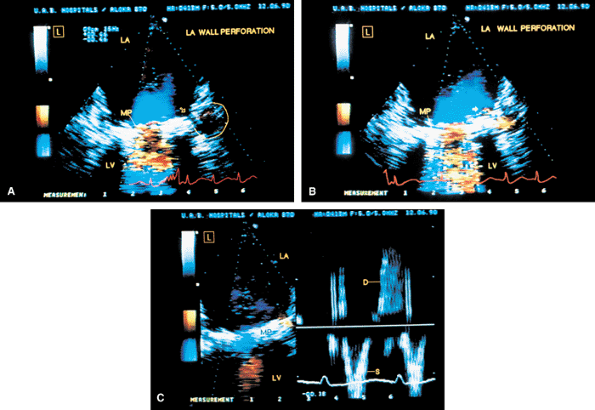

FIGURE 5.6. A–E. CarboMedics mitral prosthesis: dehiscence of left atrium (LA) wall. A. A small linear echo (vertical arrow) at the site of the paravalvular defect (horizontal arrow) consistent with suture material. B. Color Doppler examination shows a large paravalvular regurgitant jet originating at the site of the paravalvular defect (arrow) shown in A. C. An abnormal 1-cm linear echo (arrow) protrudes into the LA at the midinteratrial septal level. D,E. Multiplane views at 105° and 111° demonstrate a cavitary defect (arrows) involving the LA wall at the midinteratrial septal level, indicative of dehiscence, which explains the presence of the linear echo in the LA seen in C. F–H. CarboMedics mitral prosthesis (MP): LA pseudoaneurysm. F. A large pseudoaneurysm (AN; arrow) that developed following prosthetic replacement (MP, arrowhead) of the mitral valve.G,H. Color Doppler examination shows flow signals (arrowhead in H) moving from the left ventricle (LV) into the aneurysm cavity. AO, aorta; RA, right atrium; RMVP, reverberations from mitral valve prosthesis. (A–E reproduced with permission from Howard J, Agrawal G, Nanda NC. Transesophageal echocardiographic diagnosis of left atrial wall dehiscence. Echocardiography 1997;14:299–302. ) |